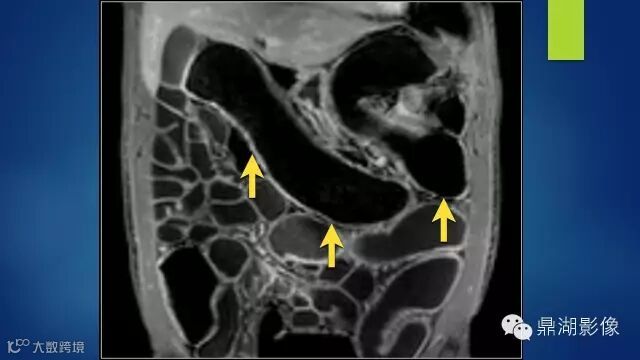

do you know comb sign?

The comb sign refers to the hypervascular appearance of the mesentery in active Crohn disease.